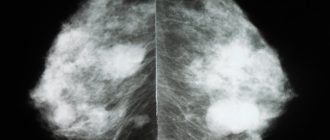

Когда назначается рентген молочных желез Рентген (маммографию) молочных желез проводят в нескольких целях. С